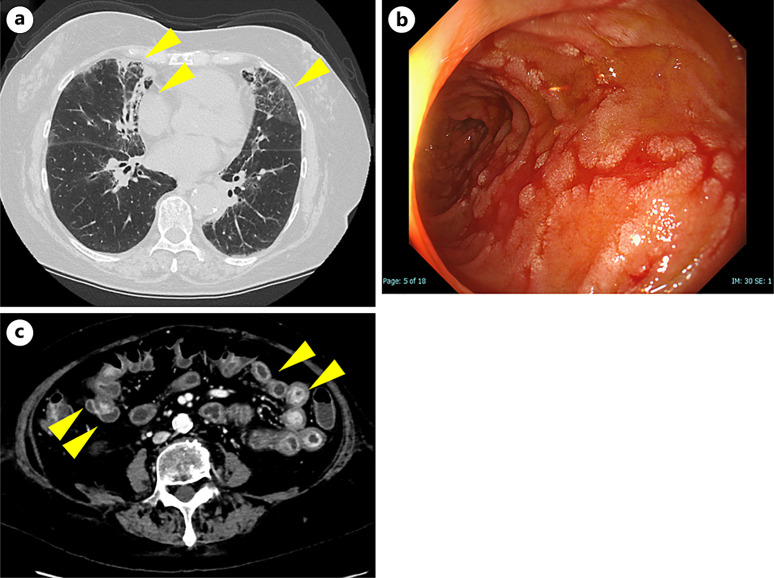

Case presentation: A 71-year-old female was diagnosed with lung adenocarcinoma (cT3N0M1c; BRN, cStage IVB [UICC-8th edition]) and was treated with pembrolizumab monotherapy, achieving a partial response. After five cycles, she developed anorexia and abdominal pain, and upper gastrointestinal endoscopy revealed hemorrhagic gastritis because of irAEs. Systemic steroids improved the gastritis, and pembrolizumab was re-administered. However, after re-treatment, she developed interstitial lung disease, enteritis, and recurrent gastritis, all of which were irAEs. Despite high-dose steroids and infliximab addition, the irAEs remained uncontrolled, and the patient eventually died.